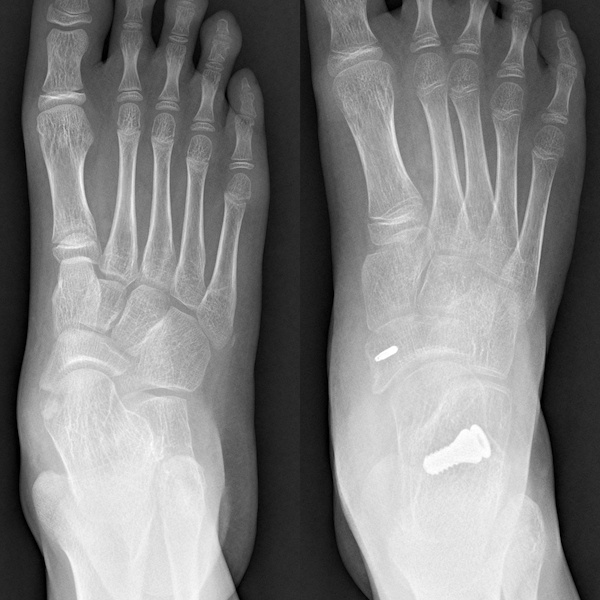

A cirurgia de órtese da articulação subtalar é uma medida de intervenção cirúrgica para o tratamento posterior do pé plano que não responde ao tratamento conservador. É um método de tratamento minimamente invasivo que corrige a deformidade do pé chato, colocando um "parafuso" entre o seio do tarso, tálus e calcâneo, conhecido como parafuso de estabilização da articulação subtalar.

Após a colocação da cinta, pode-se caminhar assim que a ferida cicatrizar, o que geralmente leva cerca de duas semanas. Para evitar o impacto a longo prazo na articulação do dispositivo colocado dentro da articulação, recomenda-se remover o parafuso de estabilização da articulação subtalar após um ano.